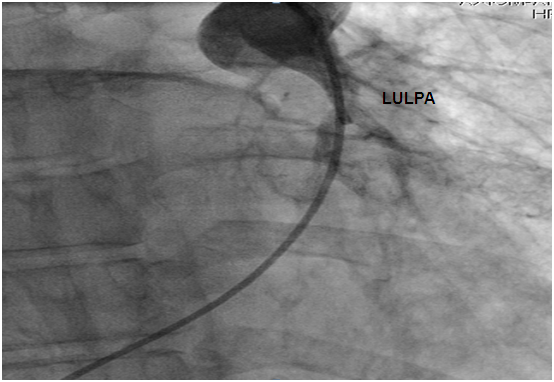

Figure 4: Hypotrophic RULPA without any veinous drainage. RULPA: Right Upper Lobar Pulmonary Artery.

Figure 5: Hypotrophic LULPA with no veinous drainage. LULPA: Left Upper Lobar Pulmonary Artery.